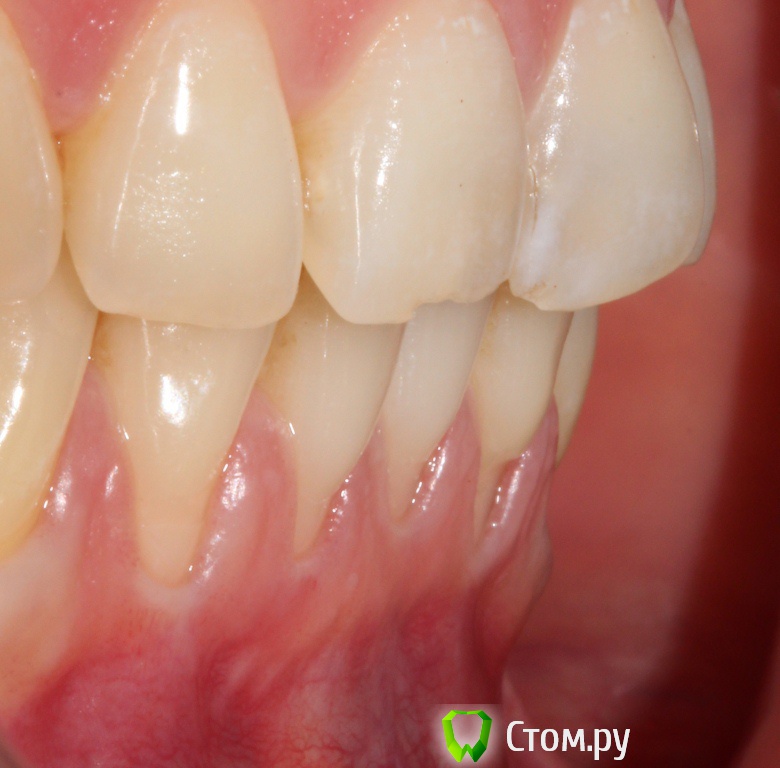

Популярный пост zzkz Опубликовано 18 сентября, 2014 Популярный пост Поделиться Опубликовано 18 сентября, 2014 (изменено) Жалобы эстетические и сильная чувствительность Рецессия от 34 до 44 Подготовка поверхности корней только скэйлинг СДТ с 2-х сторонНа небе каппа Ушивание пролен 6-0 2 недели после Чувствительности нет на сегондя. Ждать ли еще убыли или прироста? Сосочек закрыл "черный треугольник". Не уйдет ли? Изменено 18 сентября, 2014 пользователем zzkz 33 Ссылка на комментарий